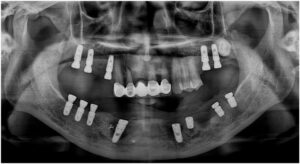

정밀한 검사를 위해

파노라마 사진을 촬영해 보았더니

아래턱 치아들이

심각한 골흡수를 보이고 있는

만성 치주염 상태로

전체 발치가 불가피한 상황이었습니다.